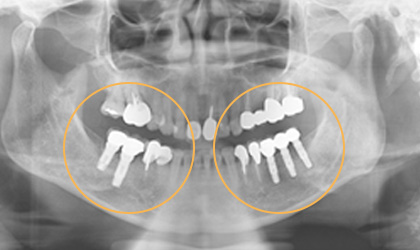

全口重建 / 植牙 ( 缺牙重建的設計考慮 )

缺一顆牙時,製作牙橋或放置一單顆植體的差別 缺牙的處理,一般有兩種方式,一是製作牙橋,另一是放置人工植牙。 牙橋的好處是製作時間快,費用可能較節省 ( 因為材質不同而有不同 ),費用大約在兩三萬附近,若含黃金比例高有可能高達6 - 7萬元 ; 但是缺點就是要修磨旁邊的牙齒,比較可惜,而且一旦是假牙,就終身是假牙,而重建的咬合也較差 ( 兩人做三人的工作 ) ,因為仍舊是少一個牙根,不過仍比不做好。 放人工牙根,也就是植牙,其最大好處就是不用修磨旁邊的牙齒,這一點其實是無價,而且完成後的咬合功能很好,幾乎和自然牙一樣,但植牙的費用較牙橋高,一顆植牙費用大約是六萬多塊到八九萬塊,會因為使用廠牌和有沒有補骨頭而有費用高低之不同,但植牙的使用年限較長,同時可避免周圍的骨頭繼續減少 ; 若照顧良好,也可能好幾十年,一般而言,十年的成功率有百分之八九十,算是非常高 ; 植牙因為要等骨頭和植體長牢,所以需要一些時間,一般上顎的牙要五、六個月,下顎因骨頭較為緻密,所以只需三四個月,但以長期的健康考慮,幾個月其實很快;以專業的建議,植牙確實比較好。

植體設計

寬直徑 vs 一般直徑

單顆雙植體 案例一